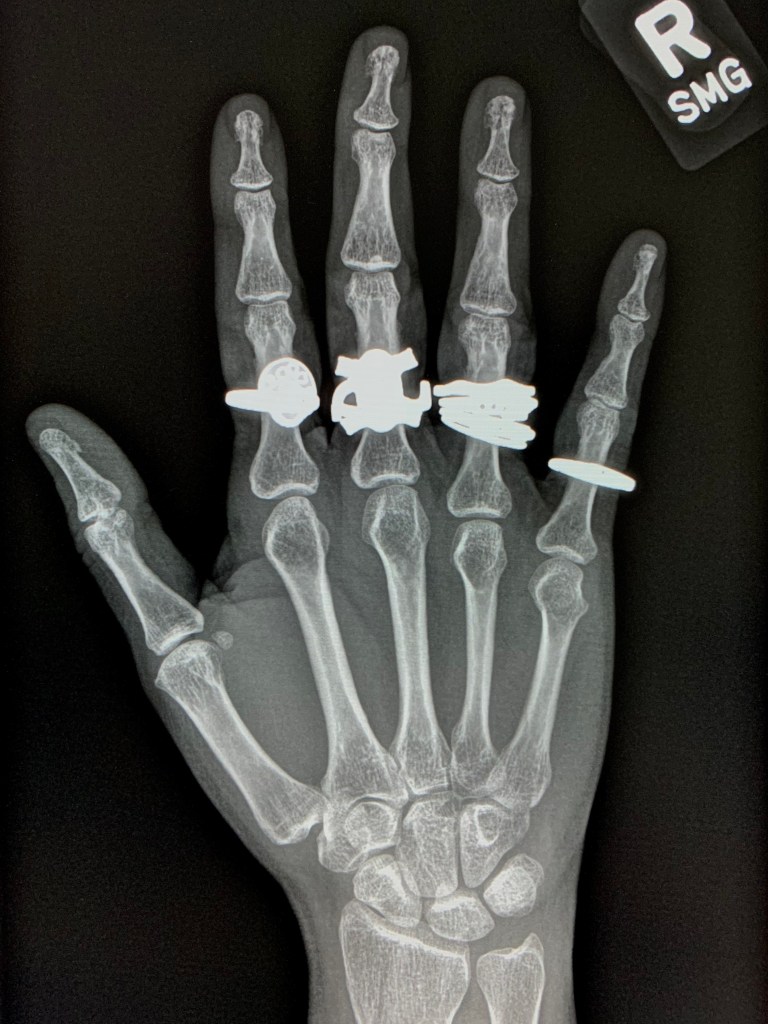

“Case of the Missing Thumb Ring”

Much of my career in radiology has been spent studying, with great fascination, the internal mechanisms of the human body. This blog is an effort to expand that view to the outside world and also to map my own experiences engaging with it. View more posts